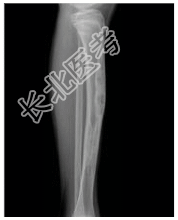

- [材料题] 患者女,10岁,左胫骨不适。查体:左胫骨压痛,皮肤无明显红肿,无明显软组织肿块。行左胫腓骨正侧位片检查。

- 简答题1、患者的诊断及依据是什么?

- 简答题2、鉴别诊断是什么?